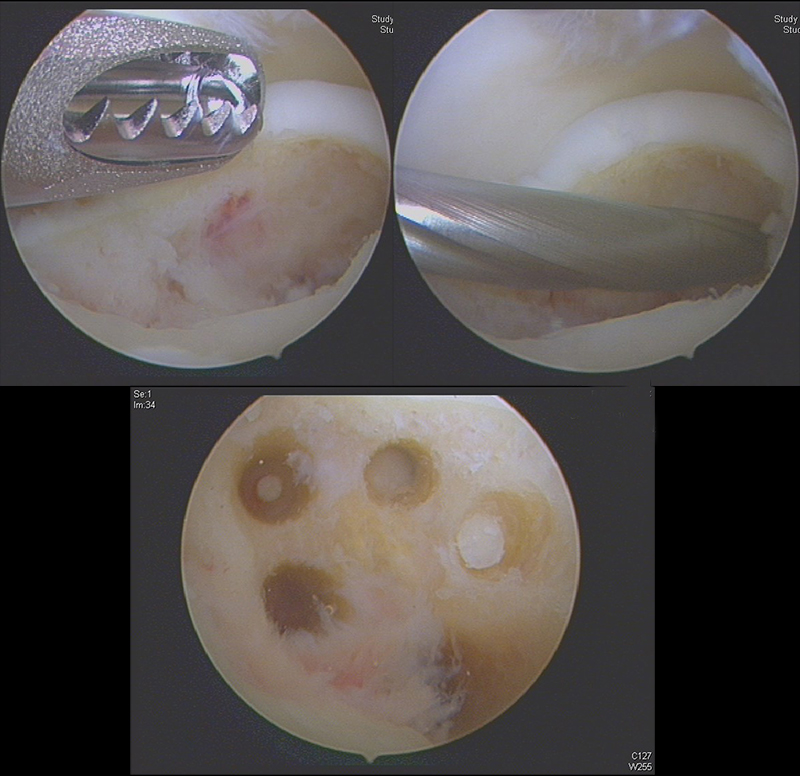

Arthroskopisches Debridement von Knorpeldefekten und Knochenmark-Stimulation

Als Knochenmark-Stimulation (KMS) bezeichnet man die gezielte Eröffnung des subchondralen Knochenmarkraumes (zumeist durch Mikrofrakturierung oder mittels Anbohrung). Intraossäre Blutgefäße werden dabei eröffnet und setzen Wachstumsfaktoren frei, welche zusammen mit den pluipotenten Zellpopulationen zur Bildung eines fibrösen Ersatzgewebes führen 8182.

Im Fall kleinerer Läsionen kann dieses Ersatzgewebe zu guten funktionellen Ergebnissen führen. Aufgrund der eingeschränkten Belastbarkeit ist der Faserknorpel bei größeren Läsionen nicht ausreichend, die hohen biomechanischen Anforderungen zu erfüllen.

Die Methode führt bei chondralen und osteochondralen Läsionen (OCL) am Talus zu überwiegend guten klinischen Ergebnissen 8586.

Chuckpaiwong et al. 87 untersuchten 105 talare OCLs, welche durch Mikrofrakturierung behandelt wurden. Dabei gab es keine Therapieversager bei Läsionen < 15 mm (n=73), unabhängig von der Lokalisation. Bei Läsionen > 15 mm (n=32) gab es hingegen nur einmal ein erfolgreiches Ergebniss. Höheres Alter, höherer BMI (body mass index), Trauma-Anamnese, und vorhandene Osteophyten wurden als negative prädiktive Faktoren identifiziert. Görmeli et al. 84 berichteten über bessere Schmerz- und Funktionsscores durch die Injektion von Hyaluronsäure bzw. PRP am Ende der Behandlung.

Zur Vollansicht und zum Lesen der Bildbeschreibung bitte das Bild anklicken.